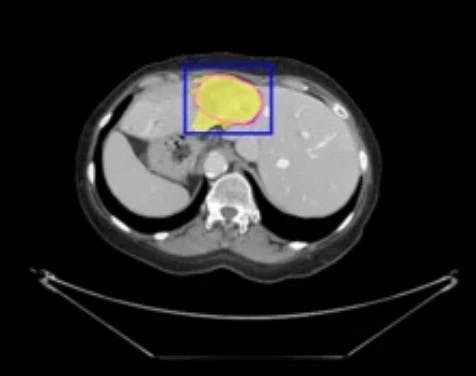

- 診断・研究の高度化

MRIやCTスキャンでの臓器・腫瘍の識別、X線画像からの異常検出、顕微鏡画像での細胞・分子構造の自動検出など、病院における診断支援や医療関連の研究プロセスの高度化・効率化を実現します。